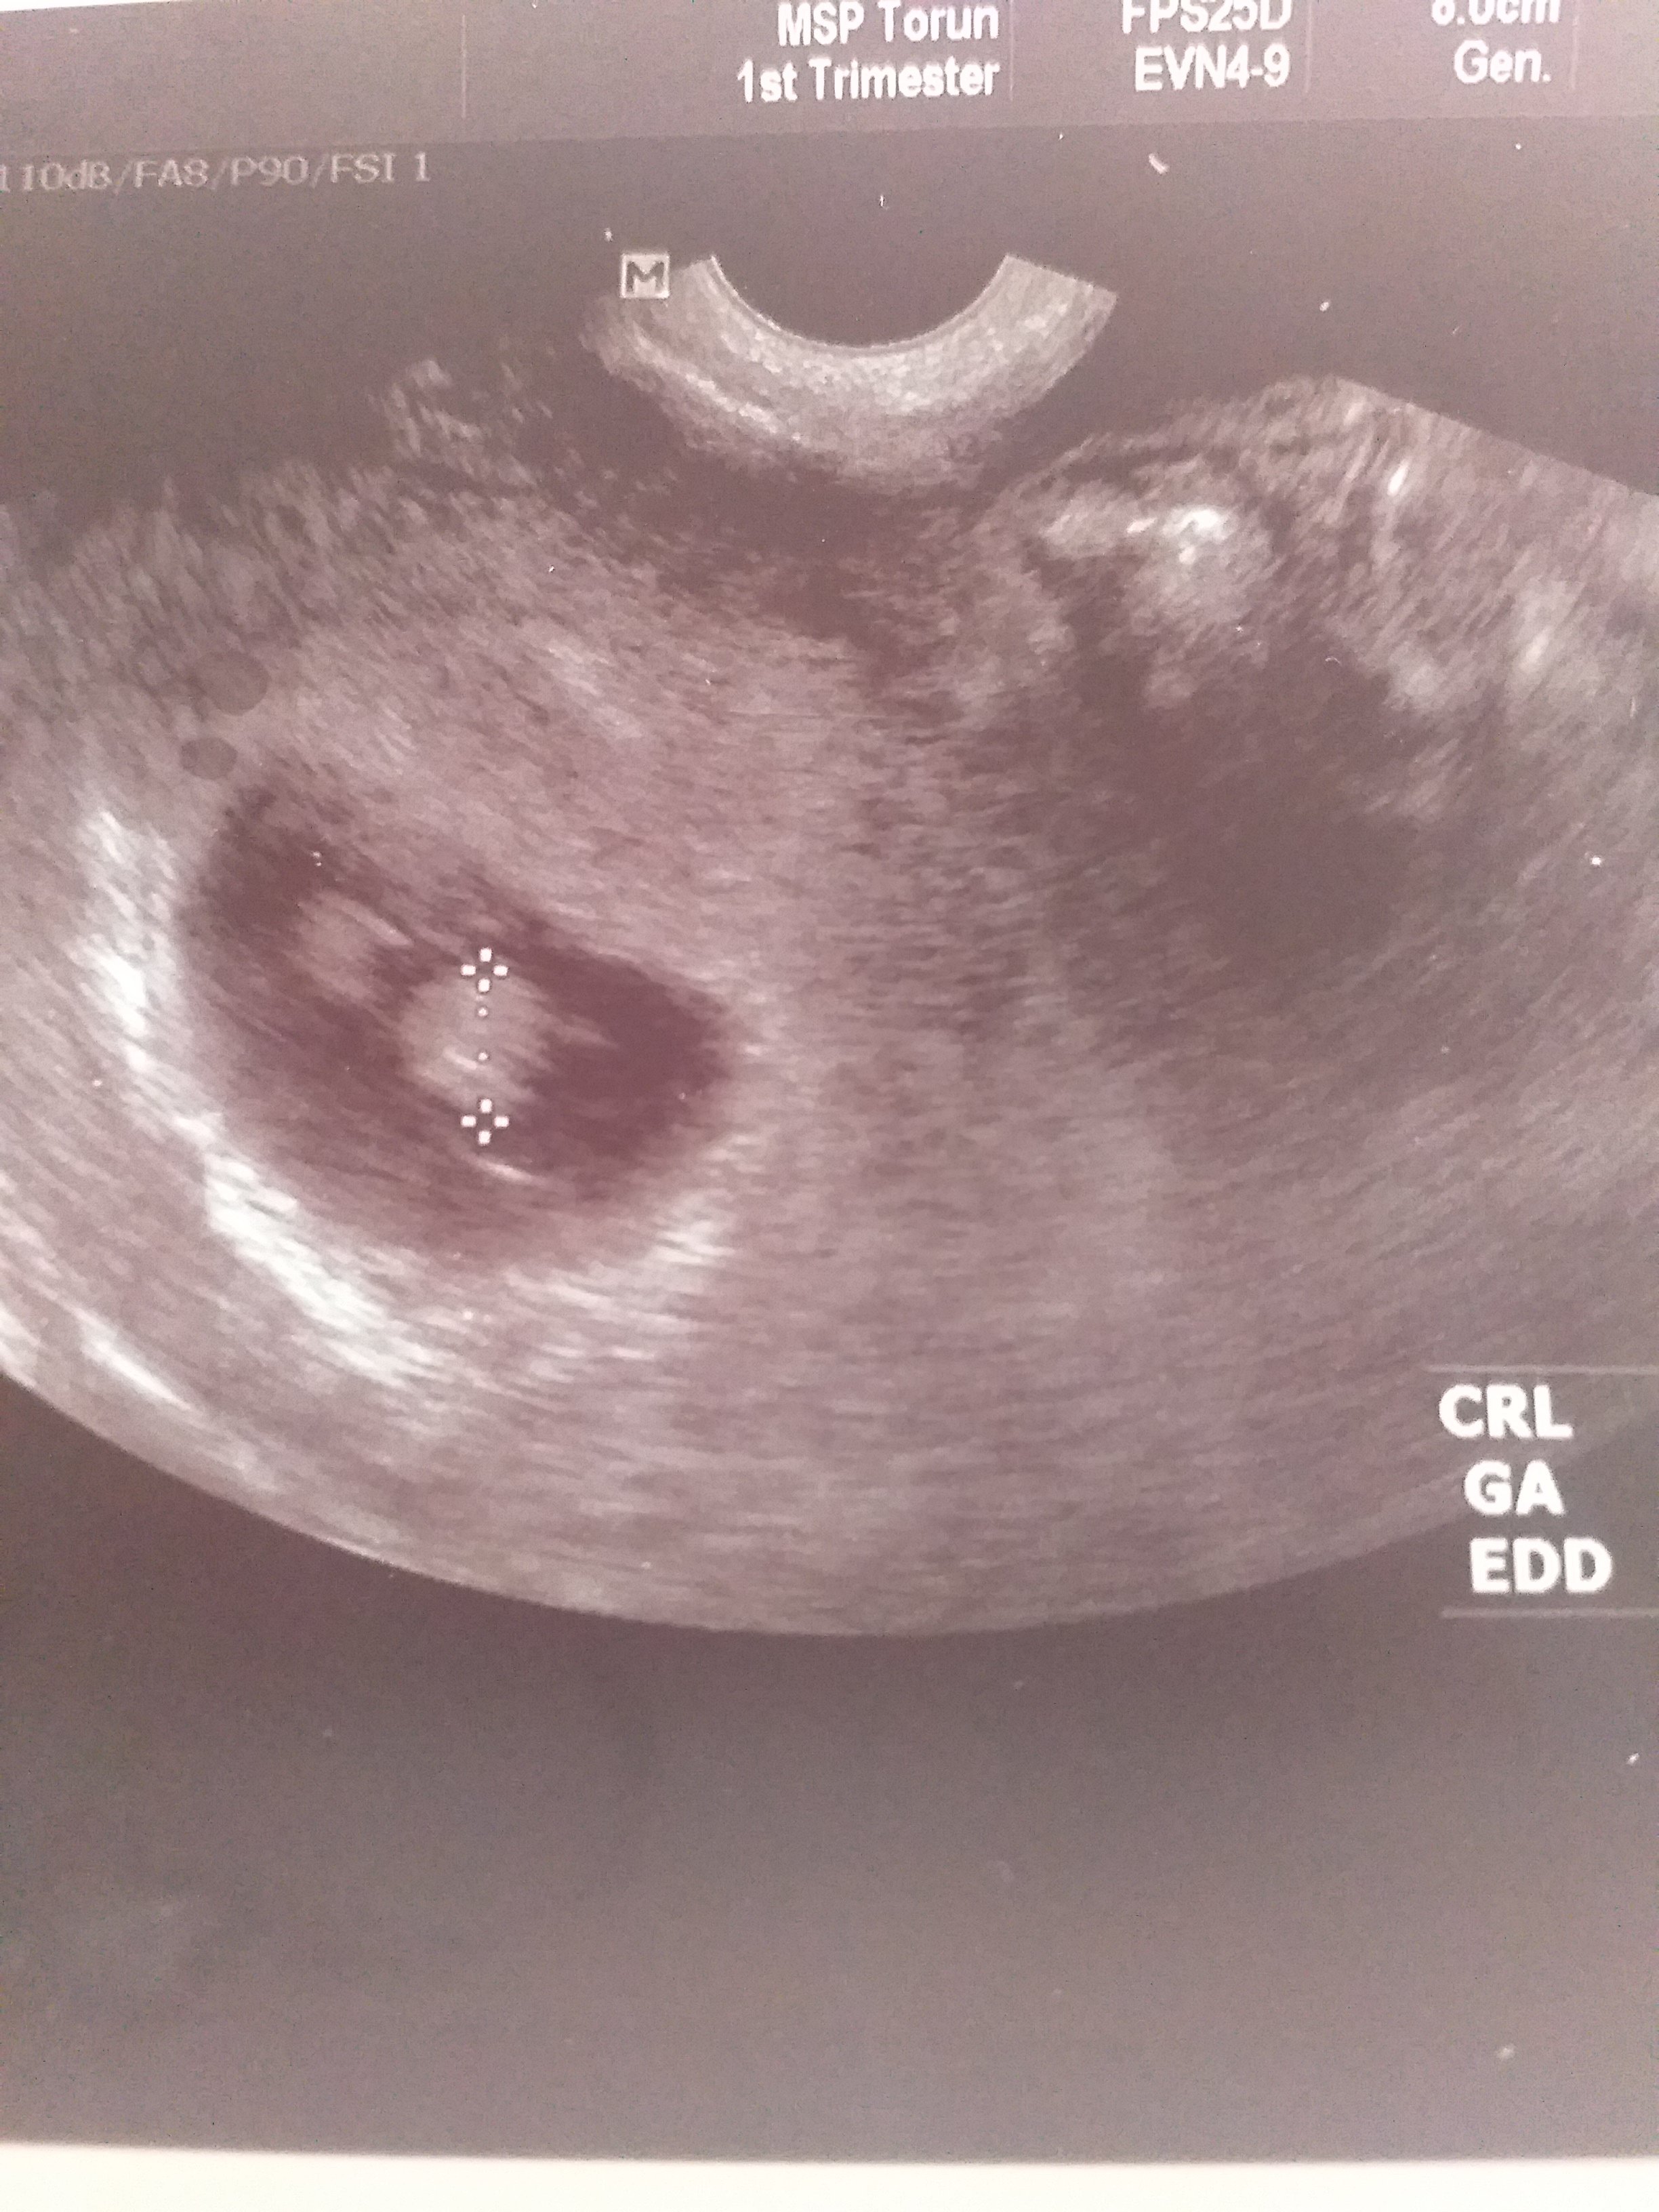

Hej wtrącę się w post bo nie wiem co robićWstawiam 5 tydz i 7 tydz. Zobacz załącznik 1109422Zobacz załącznik 1109423

A co powiedział lekarz? Może to być uchwycony jakiś narząd, a może druga dzidzia, czasem lekarz nie chce straszyć bliźniakami do puki nie ma pewności że oba dobrze się rozwijają. U mnie lekarz na słabym sprzęcie coś zobaczył, ale nic nie powiedział, za kilka dni przyjął mnie prywatnie i na dobrym sprzęcie już widział że są dobrze rozwijające się bliźniaki. Jeśli są 2jajowe to nie muszą być obok siebie, mogą zagnieździć się w zupełnie innej części macicy, moje akurat były blisko siebie.Hej wtrącę się w post bo nie wiem co robićto coś po prawej stronie co to może być? Bo chyba nie drugi płód, są tak daleko od siebie...Zobacz załącznik 1119103

No właśnie to nie był mój lekarz, poszłam do pierwszej lepszej lekarki bo nikt nie miał terminu wszystko było zamknięte przez pandemię. Lekarka była troche oschła powiedziała że serce narazie bije jedno .Jedna osoba pod moim postem napisała, że to na pewno jajnik a ja się nakrecam bo chce mieć bliźniętawłaśnie chodzi o to że mi nie zależy za blizniakach ale jest to ciąża podwyższonego ryzyka A ja mam w domu 3-łatkę i tak nic nie robię bo strasznie się czuję, a chce zdrowo donosić ciążę, jestem po jednym poronieniu. Mam predyspozycje na bliźnięta ponieważ z mojej strony są bliźnięta od rodziny babci, rodzeństwo taty to bliźnięta, siostra męża ma bliźnięta i jego kuzynka też no i w dalszej jego rodzinie też są, dodam że wszystkie przypadki to bliźnięta dwujajowe i parka

Chciałam tylko wiedzieć mniej więcej co to może być, czy to nie krwiak, no nie wiem w pierwszej ciąży nie było widać tego jajnika może teraz jest . Pozostaje mi czekać na wizytę, całe szczęście że to za tydzień![]()